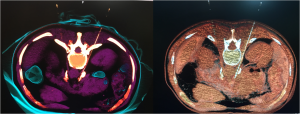

A ablação percutânea foi desenvolvido para utilização em diversos órgãos como rins, pulmão, osso, adrenal e fígado, sendo neste último a sua aplicação mais frequente. Este tratamento baseia-se na introdução percutânea (através da pele) de fina agulha (probe) pelo médico Radiologista Intervencionista, posicionando sua extremidade no interior do tumor, com apoio de recursos de imagem como ultrassonografia, tomografia computadorizada, ressonância magnética e PET-CT. Em seguida é feita uma aplicação precisa de energia geradora de calor (radioablação) ou de frio (crioablação) no interior da lesão. Na radioablação, a agulha é acoplado a um gerador que emite pulsos de radiofrequência, produzindo calor local com temperatura em torno de 80°C, suficiente para induzir a morte das células neoplásicas, ou seja, atípicas. Na crioablação, o probe gera no interior da lesão uma bola de gelo a baixíssimas temperaturas (da ordem de -140oC) que, por meio de ciclos sucessivos de congelamento e descongelamento, promove a destruição das células tumorais.

Ablação percutânea.

A imagem acima ilustra a agulha inserida no interior da lesão e em seguida  a necrose resultante deste tipo de tratamento englobando toda a massa tumoral.